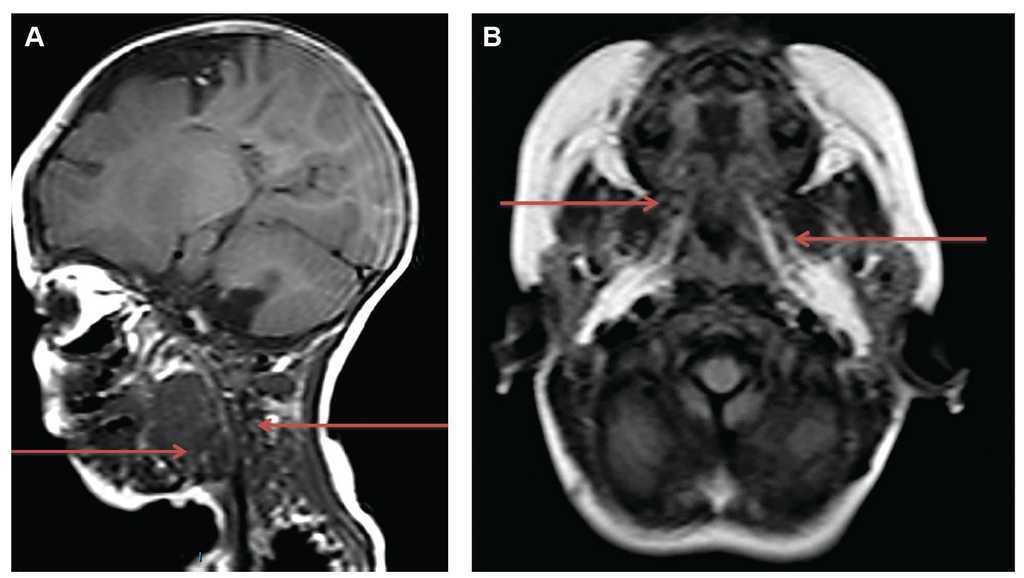

At birth, the infant demonstrated an asymmetrical neck at the expense of apparent right lateral hemihypertrophy, with extension toward the oropharynx, thus obstructing the airway and gastrointestinal tract. Neck and chest x-rays were done and showed the same narrowing of the airway and organ displacement at that level. Mechanical ventilation was initiated. Neck ultrasound revealed a cystic mass with multiple interconnected chambers and varying diameters (Fig. 1).

Figure 1 Ultrasound of the lateral neck where a multi-lobulated cystic lesion is observed. Arrows indicate some of the lobes of the cyst.